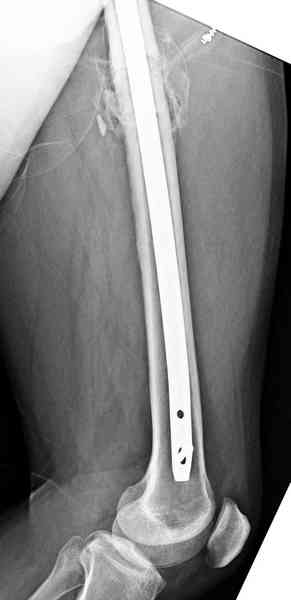

Здесь представлены снимки больного 65 лет, поступившего с диагнозом перелом

бедра после автоаварии.

В первый же день произведено антеградное штифтованием DePuy Trochanteric Nail.

На второй день (7) обнаружен пропущенный перелом,

и проведены шурурпы через и спереди штифта без удаления.

Послеоперационные снимки